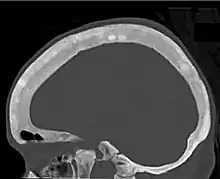

Ground glass density of the skull.[17]

CT shows focal areas of osteosclerosis.[17]